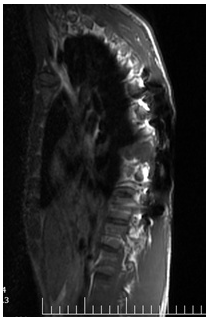

The magnetic resonance imaging (MRI) of thoracic spine revealed multiple well-defined extradural cystic lesions at T6-T8 level. There was cerebrospinal fluid (CSF) like signal intensities on T1- and T2- weighted images (Figures 3-5).

Figure 4: MRI showing extradural cystic lesions at T7-T8 level. There was cerebrospinal fluid (CSF) like signal intensities on T1- and T2- weighted images.

Figure 5: MRI showing extradural cystic lesions at T7-T8 level. There was cerebrospinal fluid (CSF) like signal intensities on T1- and T2- weighted images.